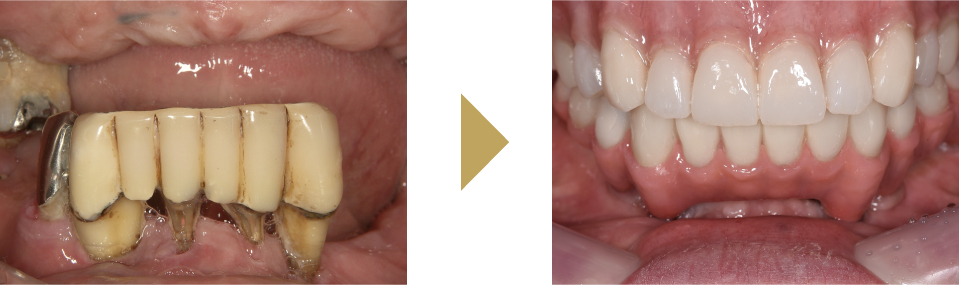

多くの歯を失った難症例にも対応します。

〜All-On-4,All-On-6〜

歯の先進国の欧米では広く普及している治療法です。

総入れ歯や多くの歯を失った方に4本から6本のインプラントをバランスよく骨に埋入して、連結した人工歯を支える治療法です。埋入手術当日に固定式の仮の歯をいれるので、その日のうちに噛む事が可能です。機能面はもちろん、審美的にも優れた治療法です。インプラント本数も少ないため、手術時間が短く、費用も抑えることが可能です。